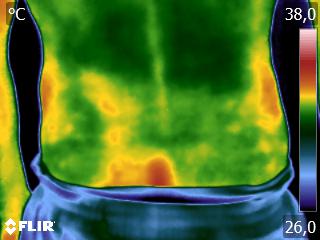

Como no caso da sequência de termogramas abaixo de uma paciente do sexo feminino, 51 anos e sem comorbidades e que sofreu um trauma de pé esquerdo durante a prática esportiva. Fez exame de Raio-X e não foi detectado fraturas, mas ainda apresentava muita dor. No 4º dia de pós trauma realizou uma Análise Termofuncional e foi detectado alterações térmicas condizente com processo inflamatório.

A terapia então foi ajustada para tratar esta lesão, não sobrecarregando a mesma e não apenas tratando a sintomatologia, mas sim até sua completa restauração.

Como no caso apresentado acima, a Termofuncional lhe proporciona não só “enxergar” as alterações térmicas, mas também uma maior segurança na terapia, com isso você poderá ter resultados muito mais eficazes. Além de lhe garantir segurança jurídica para cada procedimento que você realizar na sua reabilitação.